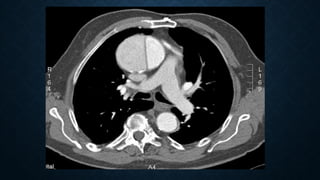

LUNG LACERATION, TYPE IV.

AXIAL CT IMAGE OF THE LEFT

LUNG AT LUNG WINDOW

SHOWS A SMALL PERIPHERAL

LACERATION BENEATH A RIB

FRACTURE SURROUNDED BY

GROUND-GLASS OPACITY

(LUNG CONTUSION) AND

ASSOCIATED WITH A SMALL

IPSILATERAL

PNEUMOTHORAX.